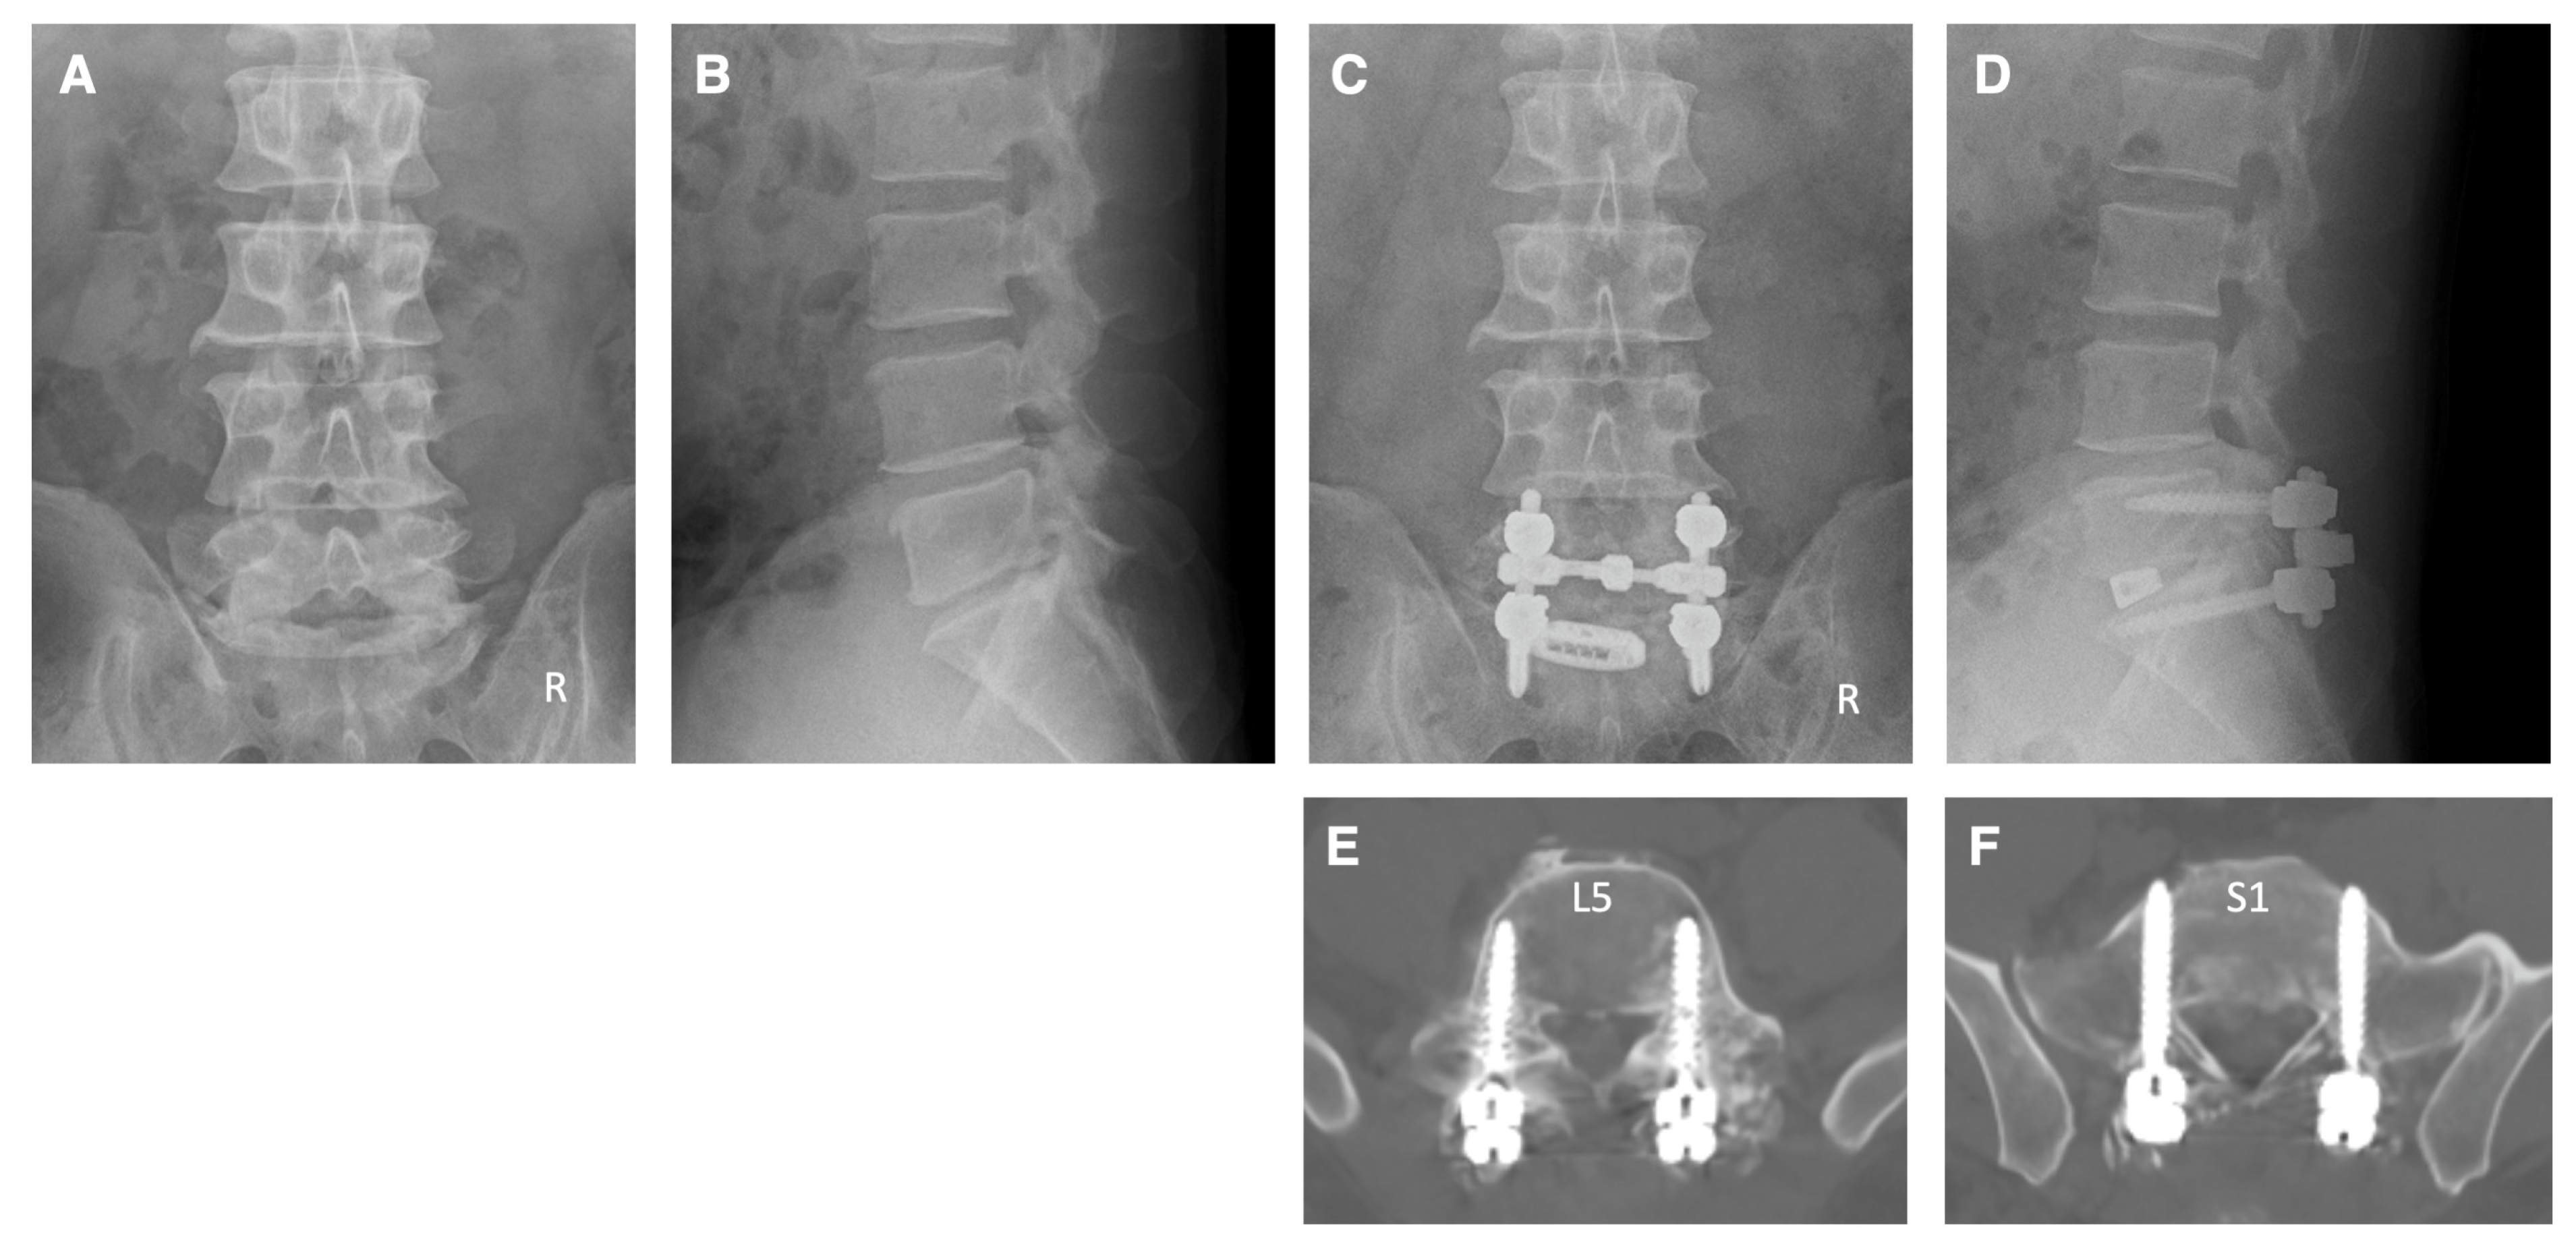

Case 1: A 42-year-old man came to our hospital with numbness in his left lower extremity and difficulty walking. The patient had L5 and S1 radiculopathy due to lateral recess stenosis and foraminal stenosis on the left side at the L5–S1 levels. Pedicle screw fixation was performed at L5–S1 levels under navigation guidance using NextAR. Decompressions of the spinal canal, left foramen, and TLIF were also performed at the L5–S1 levels. Postoperative X-ray and CT clearly showed that the pedicle screws were inserted appropriately (Figure 5). The tip of the pedicle screw at the S1 level was properly and safely penetrating the cortical bone of the promontorium of the sacrum on the CT image (Figure 5). After surgery, the numbness of the left lower limb had improved to normal, and he was able to walk without any support.

Figure 5.

Illustrative case 1. (A,B) Preoperative X-ray shows narrowing of the disc space at the L5–S1 levels. (C,D) Postoperative X-ray shows pedicle screw fixation and TLIF at L5–S1 levels. (E,F) Postoperative CT images show that the pedicle screws were inserted appropriately.